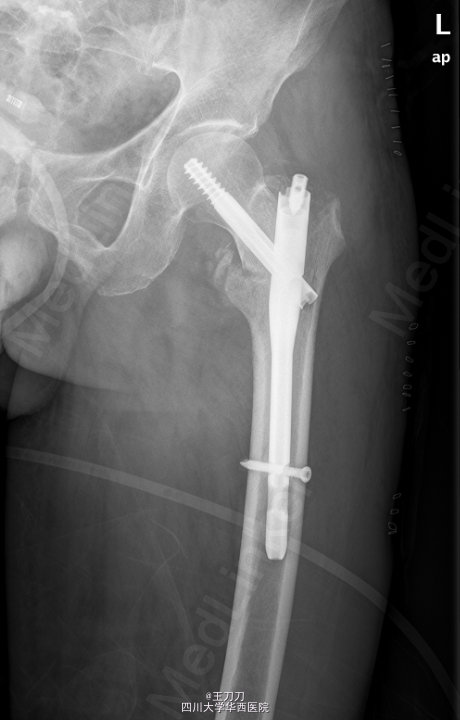

初步诊断:左侧股骨颈骨折. 在全麻下行“左股骨粗隆间骨折闭合复位内固定术”. 取以左股骨大转子顶点向近端延伸切口长约5cm,逐层切开皮肤,皮下组织,纵行分离臀大肌,臀中肌纤维,触及大转子顶点,以大转子顶点前中1/3为进针点,开口,C臂机引导下置入导针至骨折断端以远。扩髓至远侧骨折端,C臂机引导下沿导针进髓内钉至合适深度,连接锁钉支架,套筒定位后切开皮肤约2cm,C臂机引导下以合适前倾角进导针经股骨颈至股骨头前端,C臂机透视见主钉位置良好,打入防旋钉后拧入主钉,拔除导针。以适宜锁定钉行远端孔锁定,取下支架。冲洗,止血,逐层缝合至皮肤,无菌敷料覆盖。

术后14天切口拆线,卧床休息3个月,骨折愈合前禁止下地行走.